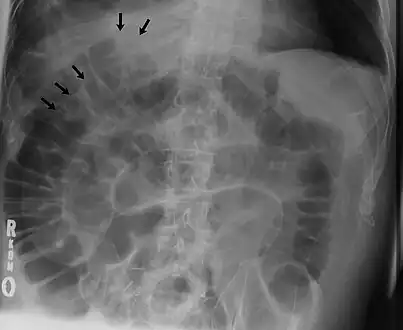

Double wall sign. This is a secondary sign of pneumoperitoneum. Patient is supine, and air within the abdomen and lumen of the bowel accentuate both sides of the bowel wall. -